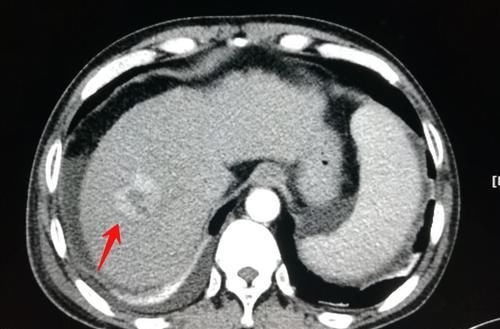

文章插图

这是一位肝硬化、脾大的病人,CT发现大量腹水和少量胸水,引起体重增加,但同时发现肝右叶肝癌。

他比较幸运,治疗效果很好!做了肝肿瘤动脉栓塞术和保肝、利尿治疗,两年多了没有复发: